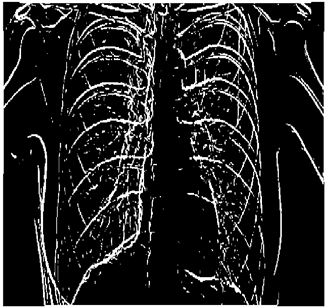

Table 5. X-ray Images.

X-ray 1X-ray 2X-ray 3X-ray 4X-ray 5

Mathematics 10 02421 i004 Mathematics 10 02421 i005 Mathematics 10 02421 i006 Mathematics 10 02421 i007 Mathematics 10 02421 i008

For the purpose of simulation, we consider two sets of images: (1) three images from MATLAB repository (Table 4) and (2) five X-ray images available online (Table 5).

Table 9 shows the following:

• In all cases, the Canny edge detector detects more edge pixels than both fuzzy compositions.

• As the level of noise increases, Canny and standard composition become adversely affected by noise, and still more edges are detected by Canny; however, most of the detected edges by Canny are misdetections due to the impact of noise. As is obvious from this table, the standard and smooth compositions provide a better image with reduced noise density.

• However, in all cases, the PFOM value for the smooth composition is always greater than the PFOM value for the standard composition, according to Table 6.